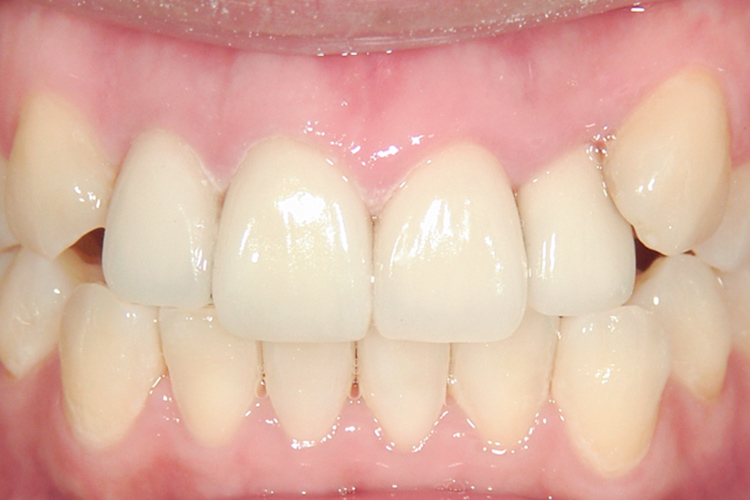

治療前

治療後